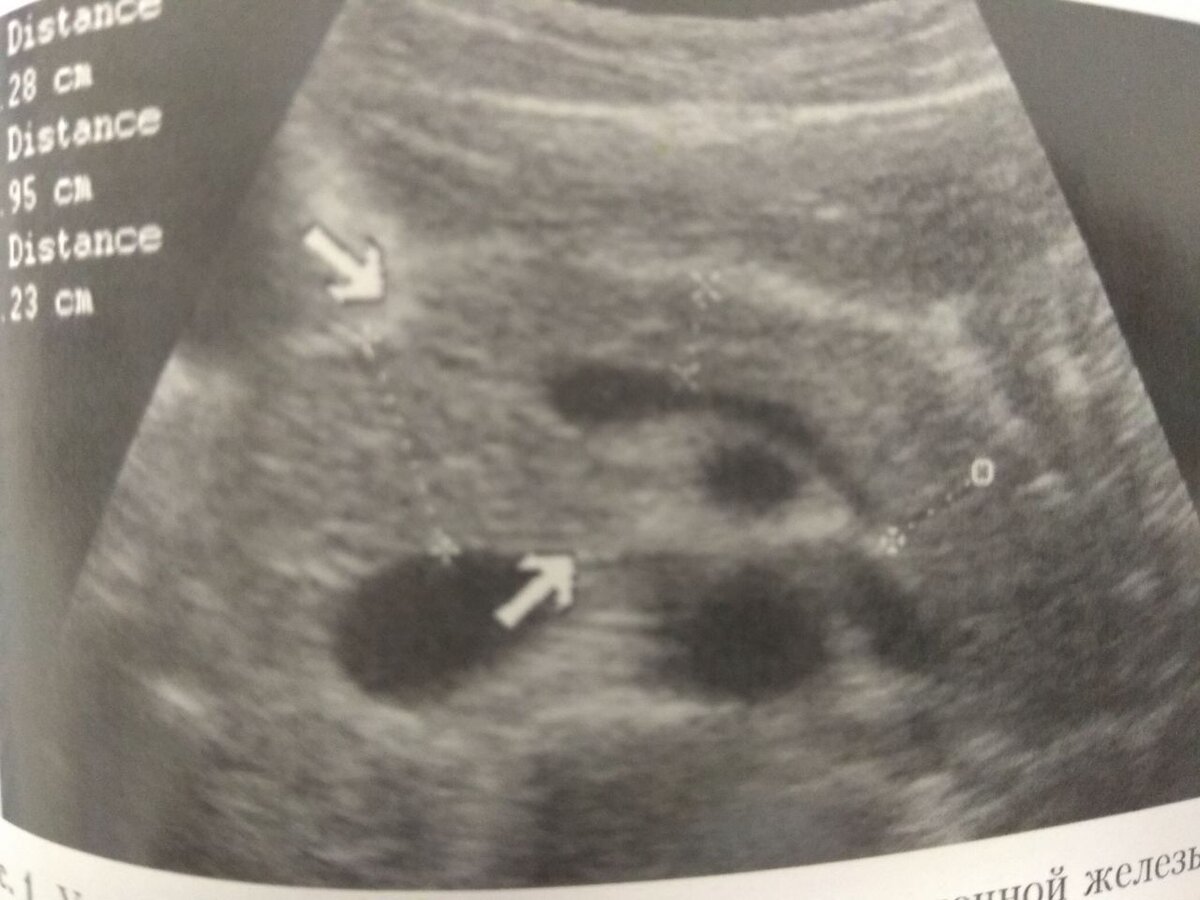

Пример расширенного главного протока поджелудочной железы (на него указывают стрелки)

Источник: Ультрасонография органов желудочно-кишечного тракта Р.Я Абдуллаев

Характеристики не осложненного острого панкреатита:

• Снижение эхогенности (изображение ПЖ становится более темным)

• Увеличение размеров ПЖ или ее структур (головки, тела, хвоста)

• Контуры железы становятся размытыми из-за отека органа

• Главный проток ПЖ расширен, его легко визуализировать. Чаще всего расширение протоки происходит в районе головки поджелудочной железы.

• Внутренняя структура поджелудочной железы становится неоднородной